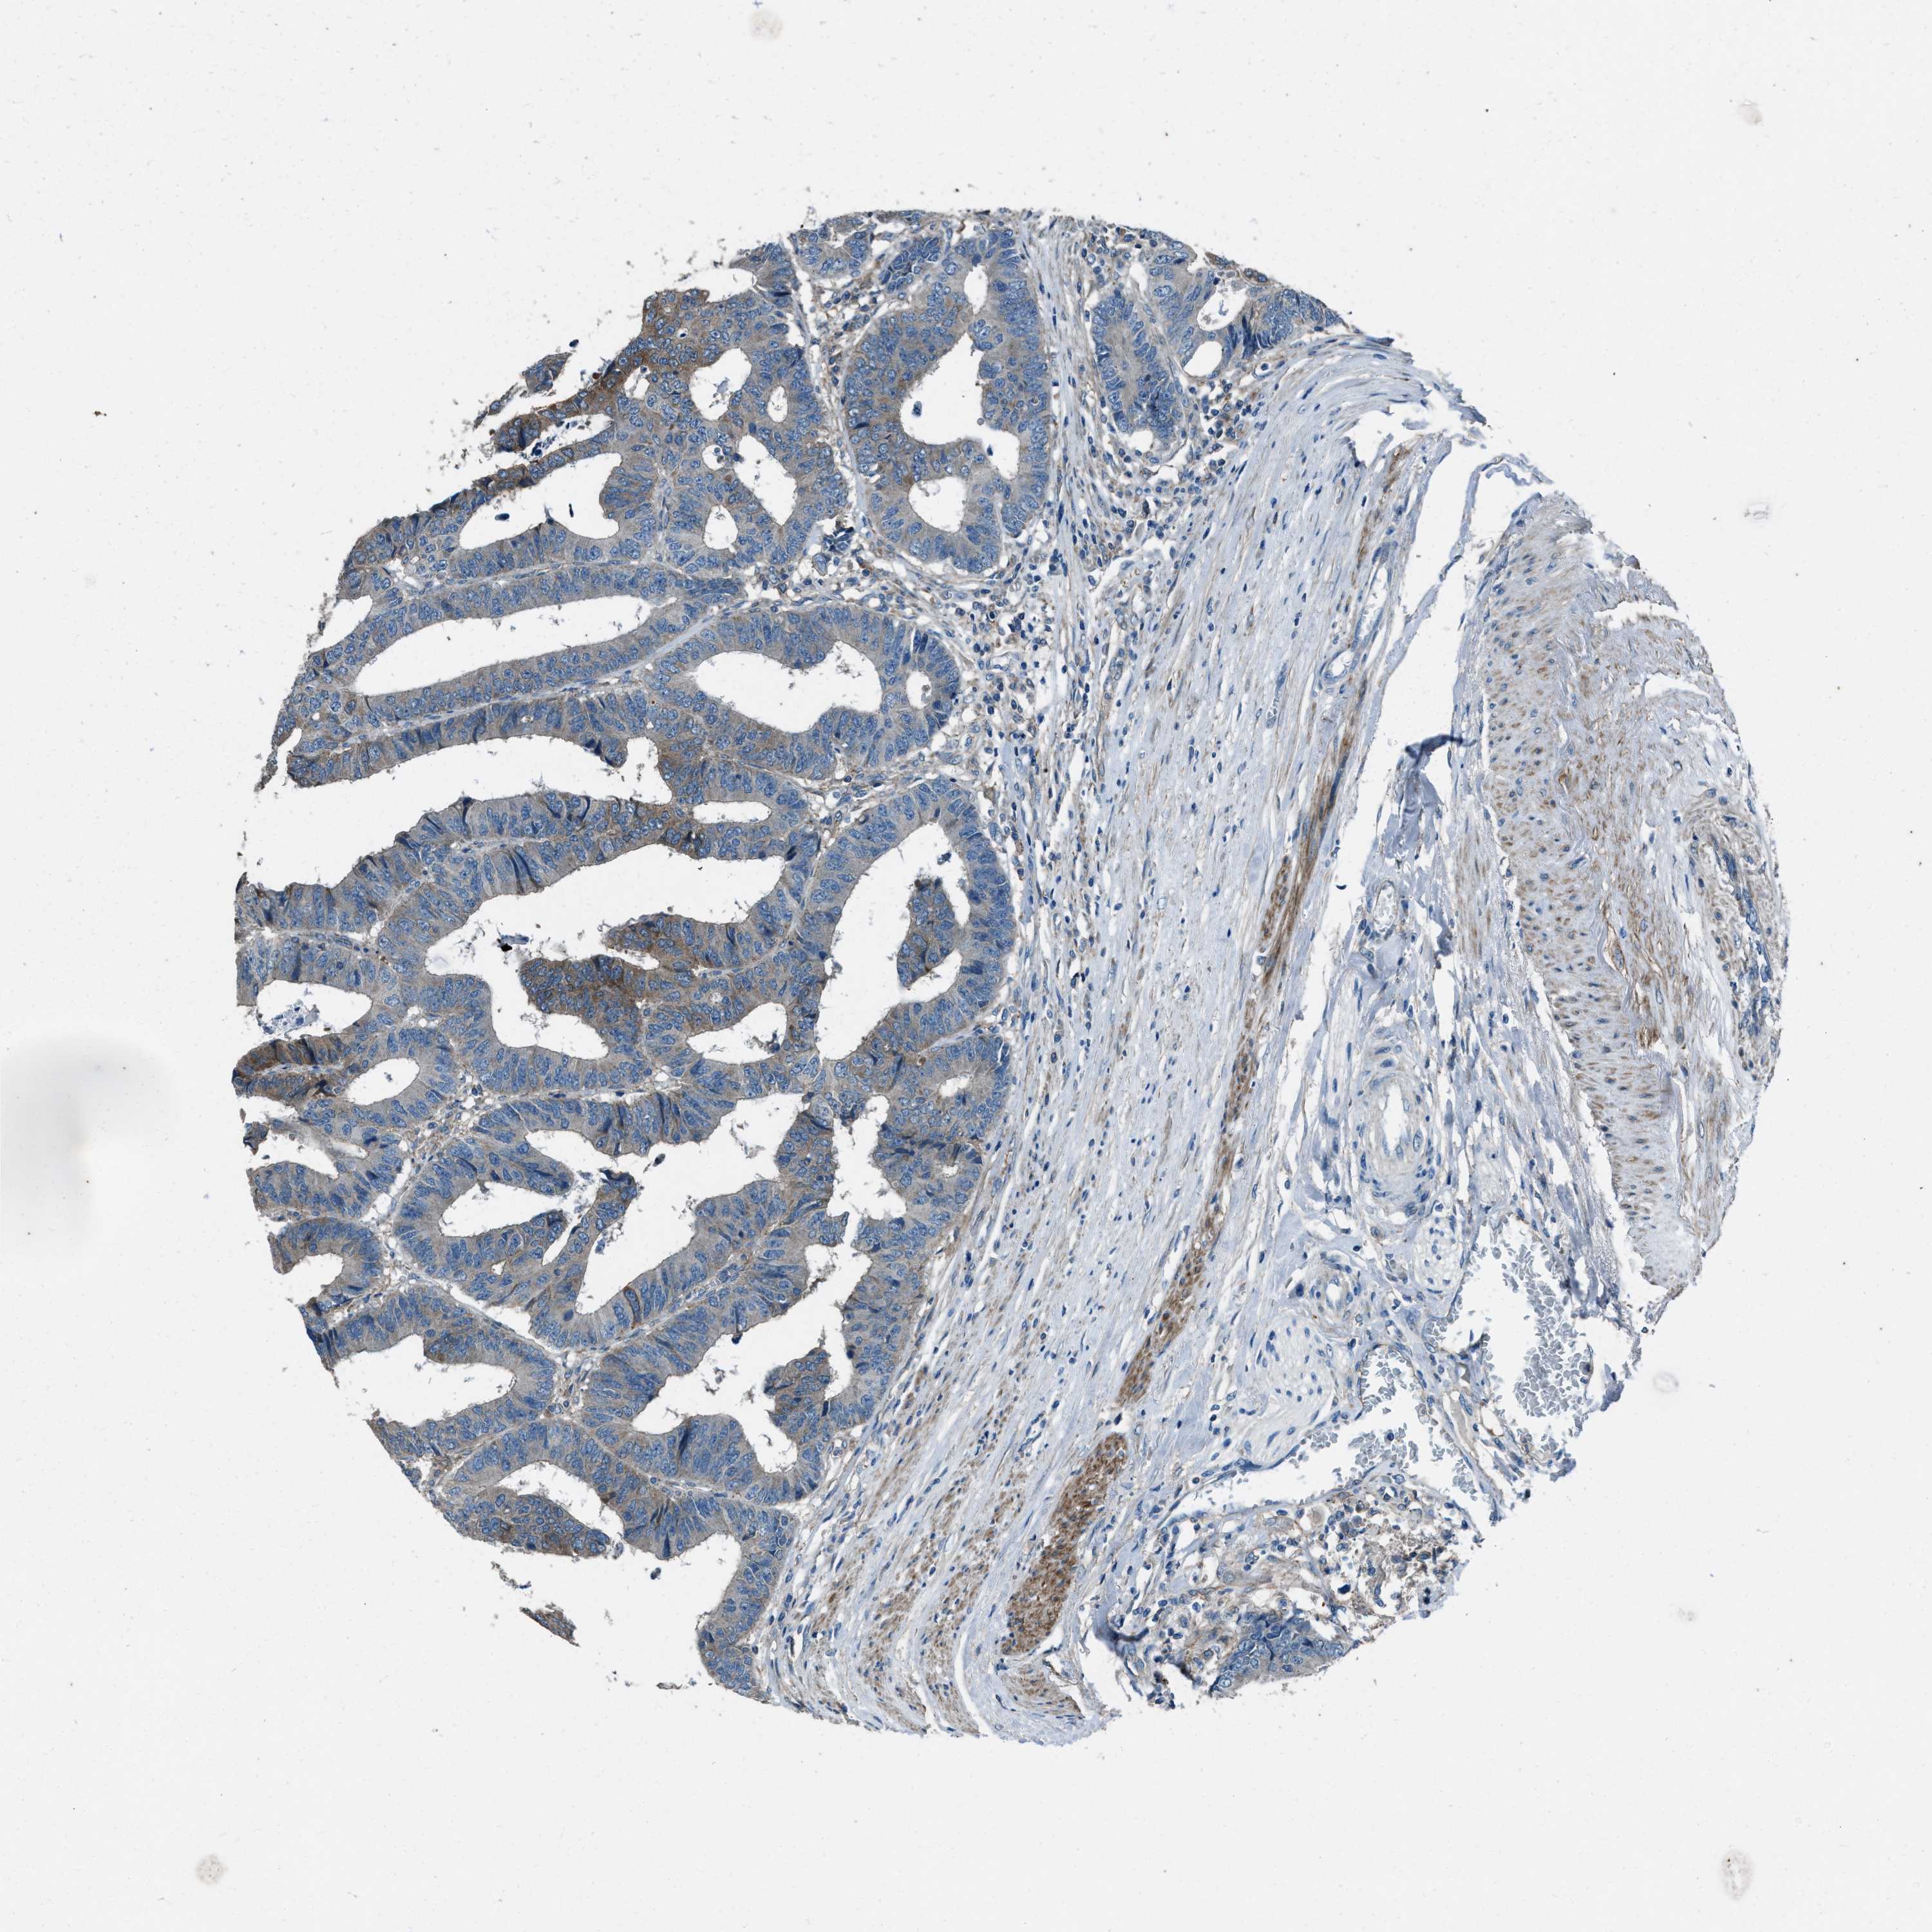

CANCER COLORECTAL CANCER Show tissue menu

COAD TCGA COAD VALIDATION READ TCGA READ VALIDATION PROTEIN COAD CPTAC PROTEIN EXPRESSION

ANTIBODIES

AND

VALIDATION